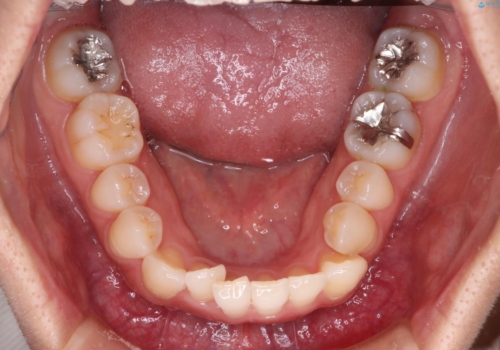

【インビザライン】前歯の凸凹をなおしたい

- 前歯の凸凹を主訴に来院されました。

上顎の急速拡大を行なったのちインビザラインにて治療を行なっております。

今回のケースは後戻りのリスクを低くし、またディスキング量を減らすために上顎の急速拡大を行なっております。